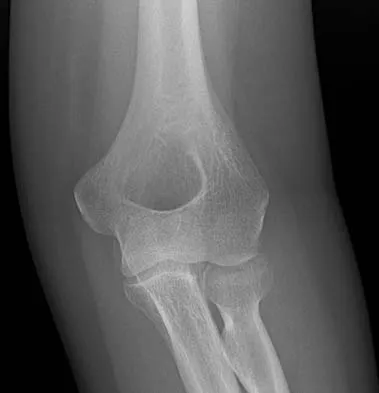

A 78-year-old woman falls onto her nondominant left elbow and sustains the injury shown in Figure 5. What treatment option allows her the shortest recovery time and highest likelihood of good function and range of motion?

Total elbow arthroplasty has become the treatment of choice for complex, comminuted distal humeral fractures in patients older than age 70 years. It yields a faster recovery with more predictable functional outcomes, although limitations of lifting weight of more than 5 pounds must be followed to avoid loosening. Kamineni S, Morrey BF: Distal humeral fractures treated with noncustom total elbow replacement. J Bone Joint Surg Am 2004;86:940-947.